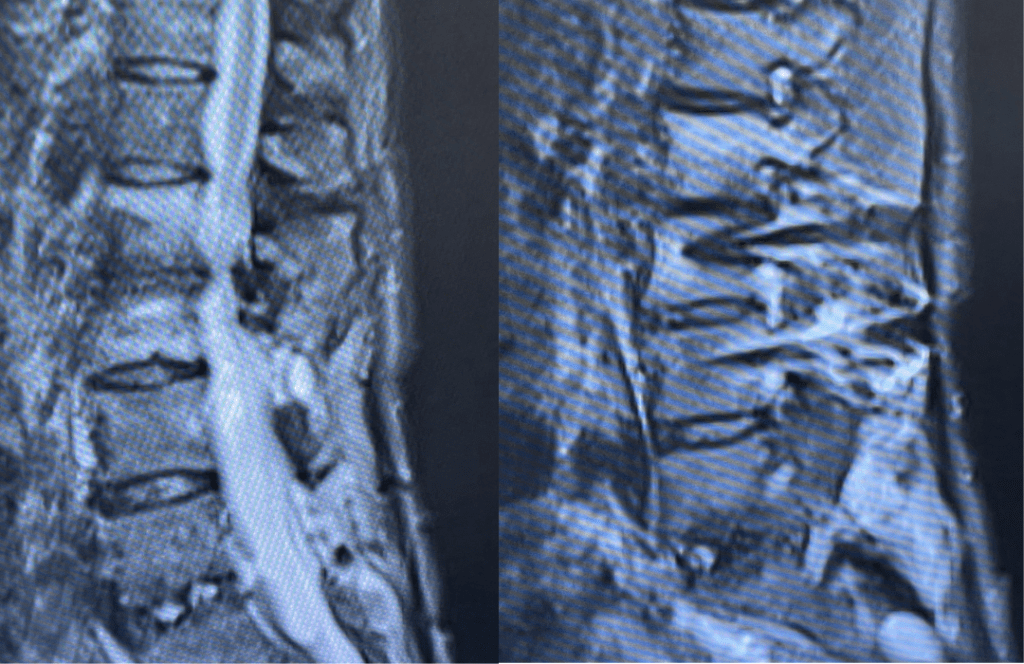

Spine:

Thoracic Spinal Cord Tumor Case Presentation

Author: Xavier P. J. Gaudin D.O., F.A.C.O.S., Read More!